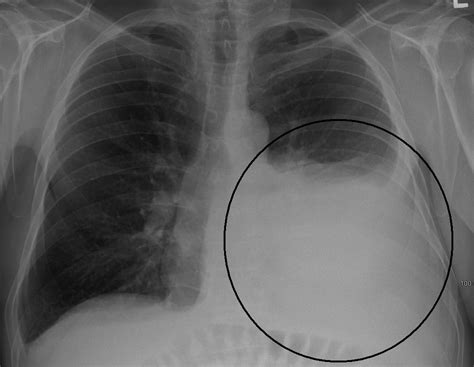

Derrame Pleural A Esquerda

Webun derrame pleural es una acumulación anormal de líquido en el espacio pleural. Webderrame pleural é definido como acúmulo de líquido no espaço pleural. Normalmente, esse espaço está preenchido por uma fina camada de líquido. Webnas radiografias em pa, vemos dois pacientes com derrame pleural à esquerda, com sinal da “parábola de damoiseau” marcado em azul.